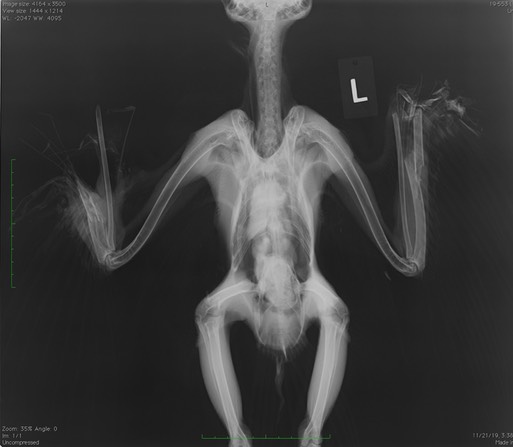

We do not know how the owl was injured, but both of its wings were partially amputated. It was humanely euthanized.